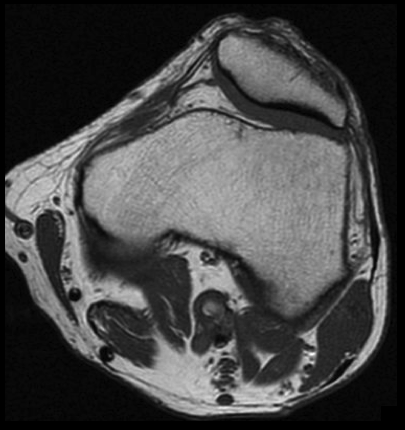

2. Tras analizar los cortes en planos axial y coronal, ¿cuál crees que es la causa de la obstrucción de la arteria poplítea izquierda?

- A. Ateroesclerosis.

- B. Enfermedad quística adventicial.

- C. Síndrome de atrapamiento poplíteo.

- D. Aneurisma trombosado.

- E. Enfermedad de Berger.

3. Para confirmar los hallazgos de la angioTC de extremidades inferiores, se realizó RM de rodilla izquierda. ¿Qué hallazgo se observa en la secuencia axial SE T1?

- A. Aneurisma poplíteo trombosado.

- B. Quiste adventicial en la pared de la arteria poplítea.

- C. Banda muscular anómala rodeando a la arteria poplítea.

- D. Exóstosis de tibia comprimiendo la arteria poplítea.

- E. Flap intimal intraluminal.